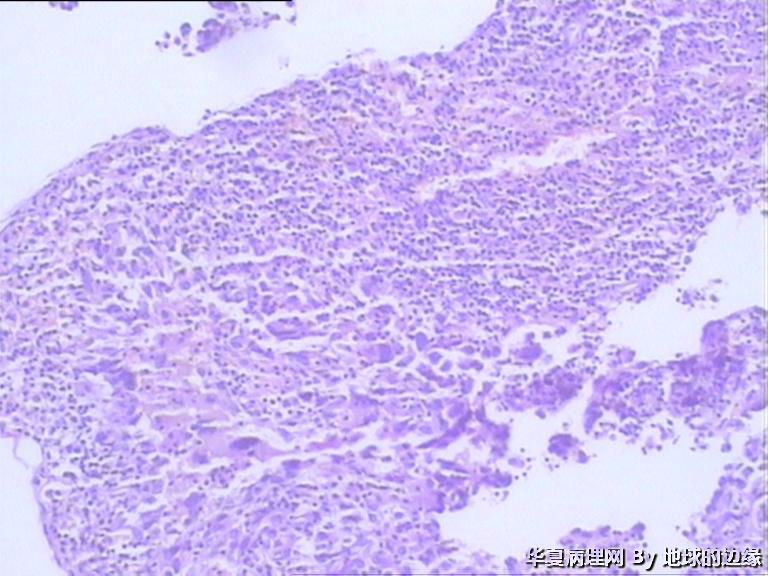

右肱骨肿瘤待查

病人女性,48岁

MRI示:右肱骨肿瘤待排,包块大小为10x8cm,活动度差,边界欠清,鱼肉组织(白色),肿块侵犯至骨外    组  织。

恶性。是转移还是原发,是骨肉瘤还是浆母?需要进一步资料并标记。

考虑肉瘤,转移癌也排除一下吧

目前Vimentin阳性,P53阳性,AFP,EMA,CK7,CK20,E-ca,CR,PLAP,CD99,ER,PR,CEA,均阴性,只是没做淋巴瘤这一套了